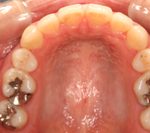

3) 矯正を終えた状態

![]() |

||

叢生(そうせい…歯がデコボコしたり、重なりあって生えていたりする状態)

開咬(かいこう…奥歯はしっかり噛んでいるが、上下の前歯が噛まずに隙間がある状態)